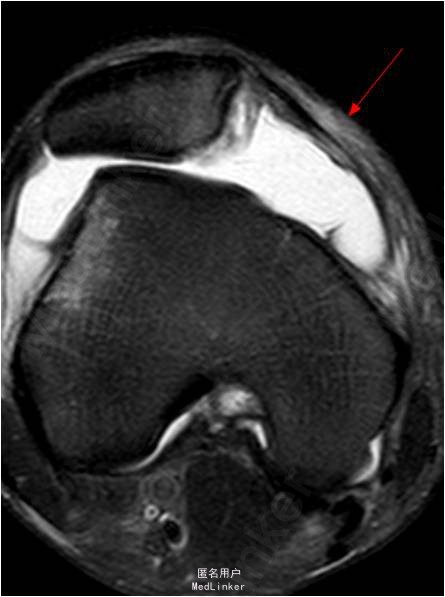

患者男,20岁,因”扭伤后右膝关节疼痛3周”入院。患者受伤时自觉右膝髌骨往外脱位,后自行复位。

查体:右膝关节无肿胀,浮髌征(-),髌骨恐惧试验(+),研磨试验(+),ADT(-),lachman征(-),麦氏征(+),PDT(-),侧方应力试验(-),关节活动度0-135度,股四头肌无明显萎缩,肌力正常;肢端血运、感觉、活动正常。MR提示:1.右膝髌骨脱位:MPFL损伤;2.右膝关节半月板损伤

诊断:1.右膝髌骨脱位:MPFL损伤 2.右膝关节半月板损伤 行右膝关节镜检,半月板修补,关节镜监视下MPFL探查+修补术